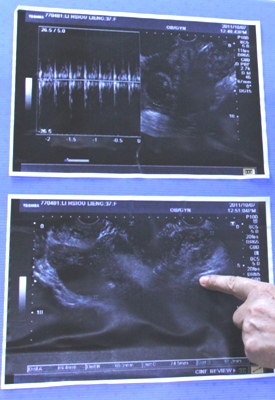

依據衛生署國民健康局於2007年委託進行之「台灣地區高血壓、高血糖、高血脂之追蹤調查研究」結果,50歲之前女性的高血壓、高血糖及高血脂發生率普遍低於同年齡層的男性,但值得注意的是女性在更年期後,三高發生的比率大於男性,顯示女性更年期後,三高是一個不能輕忽之健康議題。(圖:2002至2007年國內民眾不同性別及年齡層之高血壓發生率)